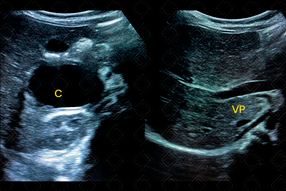

Texto alternativo para a imagem Figura 1. Créditos: Dra. Elazir Mota - Rio de Janeiro/RJ

Descrição da figura 1: Ultrassonografia de abdome. Paciente do sexo feminino, 4 anos, com queixa de dor abdominal e vômitos. Presença de imagem cística (C), adjacente ao duodeno e lobo direito hepático, sem evidente comunicação com duodeno, exercendo somente efeito compressivo.

• Ultrassonografia de abdome: Por tratar-se de uma doença com pico de incidência na infância, o exame de escolha será a ultrassonografia, por conta de seu baixo custo, acessibilidade e livre de radiação ionizante. Na imagem, o cisto de duplicação apresenta uma característica patognomônica: double wall sign , com sua parede interna hiperecogênica (representando mucosa/ submucosa) e parede externa hipoecoica (muscular) (f iguras 1 e 2);